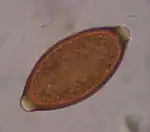

Détection

Ce parasite peut être mis en évidence par un examen parasitologique des selles chez le sujet infesté.